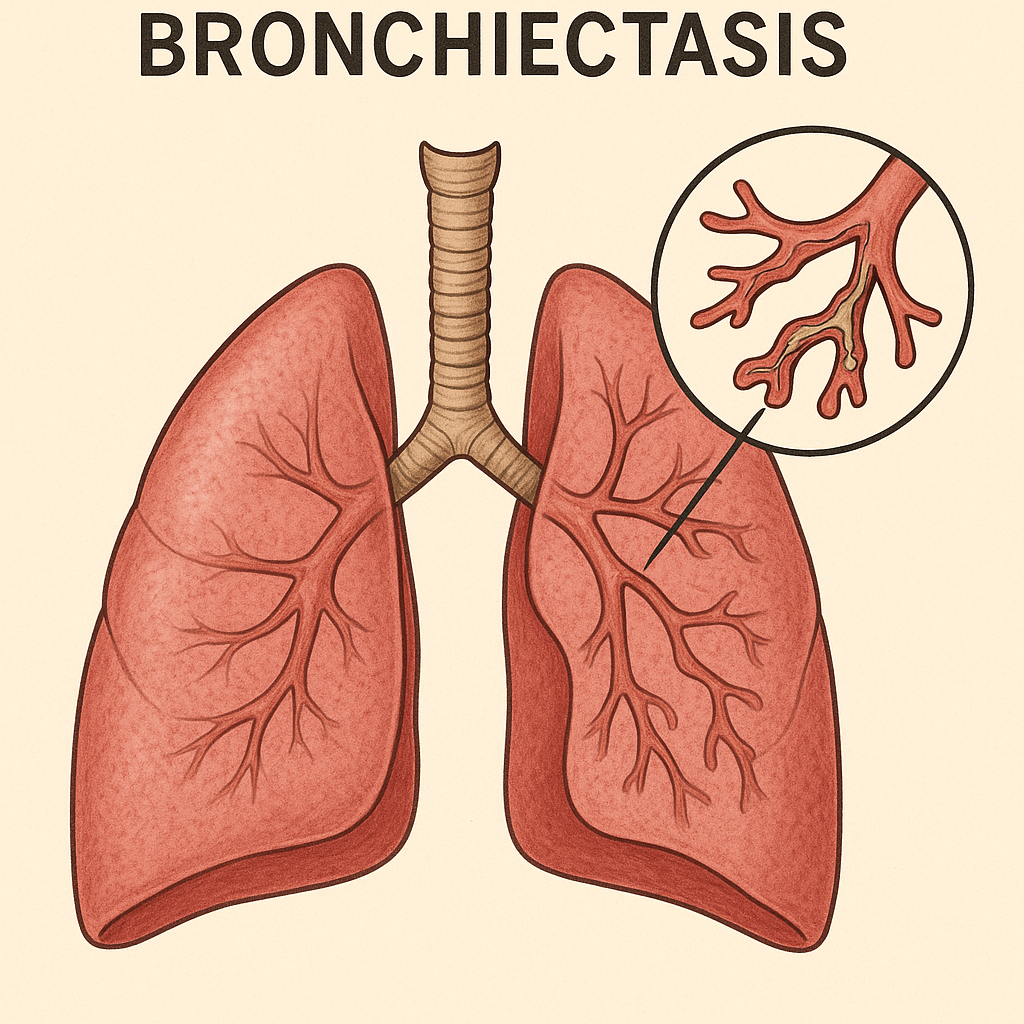

# Respiratory

Chronic Obstructive Pulmonary Disease (COPD)

क्रोनिक ऑब्स्ट्रक्टिव पल्मोनरी रोग (सीओपीडी)